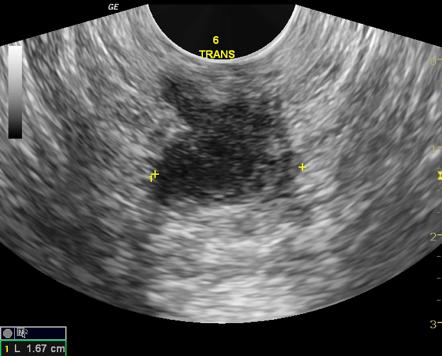

超音波(エコー)検査(簡便ですぐにできる検査)

超音波検査は、簡便に行えるため、膿瘍の位置や大きさを確認する初期検査として用いられることがあります。リアルタイムで観察できるため、膿の溜まり具合を確認しながら検査ができます。

超音波(エコー)検査イメージ:皮膚に近い膿瘍の位置や大きさを確認します。